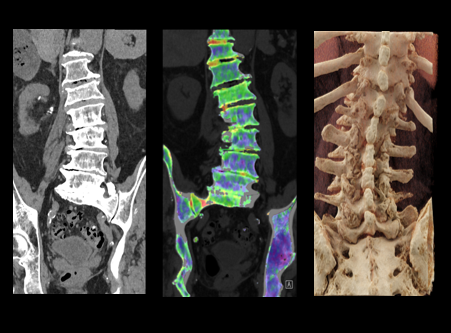

다음과 같은 검사가 가능합니다.

* 이해를 돕기 위한 이미지이며, 실제 촬영 시 이와 상이할 수 있습니다.